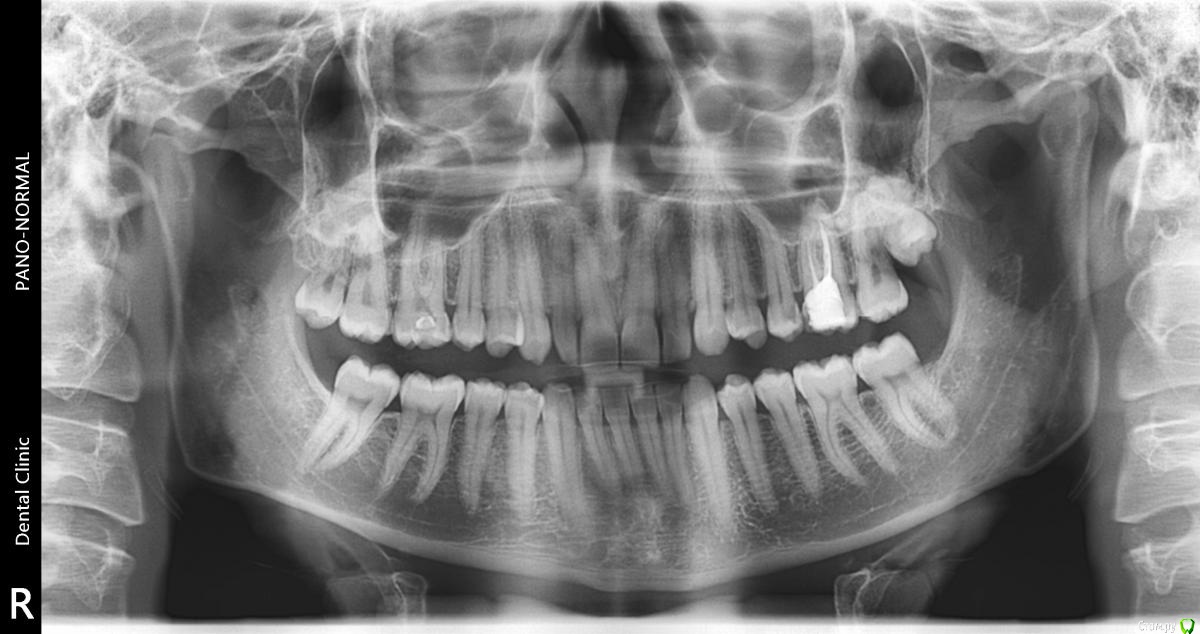

Dench Опубликовано 6 февраля, 2017 Поделиться Опубликовано 6 февраля, 2017 (изменено) Добрый день, уважаемые! Просьба помочь определиться с дальнейшей тактикой: лечить или удалять 26 зуб. На руках имеется панорамный снимок и КТ с расшифровкой. После панорамы у терапевта возникло подозрение на кисту у корня 26 зуба. Панораму делал совершенно случайно в детской стоматологической клинике. Для подтверждения диагноза сделал КТ размером 12 на 8,5, заключения следующие:2.6 зуб — депульпирован. Коронковая часть — восстановлена пломбой с нарушениемкраевого прилегания — удалено администраторомна мезиальной контактной поверхности на 2/3 толщиныдентина. Вариант строения — три корня, ДЩ и небный корни срослись между собой / четыре канала, МЩ корень имеет два канала, открывающихся одним апикальным отверстием. МБ1 канал, канал ДЩ корня и канал небного корня негомогенно, неплотно обтурированы пломбировочным материалом на 2/3 длины каналов, на остальном протяжении каналы облитерированы. МБ2 канал свободен от пломбировочного материала. Определяется расширение периапикального периодонтального пространства МЩ корня шириной до 0,8 мм, небного корня шириной до 0,9 мм.Пародонт: патологической убыли костной ткани не выявлено.На томограммах и реконструктивных снимках околоносовых пазух и полости носаустановлено следующее:В/ч синусы гиперпневматического типа. Контуры видимых стенок четкие, не прерываются. Определяется утолщение слизистой оболочки в/ч синусов: справа до 2,4 мм, слева до 2,8 мм. В толще слизистой оболочки нижней стенки левого в/ч синуса определяется зона повышенной плотности с четкими, ровными контурами, овальной формы, не связанная с костными стенками левого в/ч синуса, не нарушающая целостность кортикальной пластинки, размерами 3,1х1,8х2,7 мм (ШхВхГ).ДИАГНОСТИЧЕСКОЕ ЗАКЛЮЧЕНИЕ:Частичная вторичная адентия.Ретенция зуба 2.8.удалено администраторомзубов 1.5, 2.5, 3.5, 3.6 (?).Вторичный удалено администратором зубов 1.6, 2.6.Хронический удалено администратором зуба 2.6.Двустороннее утолщение слизистой оболочки в/ч синусов.Зона повышенной плотности в толще слизистой оболочки левого в/ч синуса (кальцинат).Терапевт настаивает на удалении. Был у хирурга. Его мнение - зуб не удалять, а лечить. Если все же решусь удалять зуб, то возникают следующие сомнения (основаны на моих догадках):- так как пазухи гиперпневматического типа, то существует вероятность перфорации пазухи с дальнейшими осложнениями и необходимостью пластики сообщения полости рта с вч пазухой?- так как зуб кариозный, то в процессе удаления он может расколоться на части и неизбежно перфорировать пазуху или что еще хуже попасть внутрь пазухи?Если все же удалять зуб, то удалять его следует в ЧЛХ или хирург при возникновении осложнений в процессе удаления сможет их устранить? Во вложении панорамный снимок (качество снимка, со слов хирурга, плохое) и несколько прицельных снимков 26 зуба и панорамный реформат из КТ.Заранее спасибо за ответ! Изменено 6 февраля, 2017 пользователем red_butler ссылки на сторонние ресурсы Ссылка на комментарий

Dench Опубликовано 16 апреля, 2019 Автор Поделиться Опубликовано 16 апреля, 2019 (изменено) ЗУБ 16. В итоге зуб перелечил год назад под микроскопом, нашли ещё один канал. В настоящий момент периодически (кратковременно 2-3 раза в месяц) при надавливании на зуб ощущается давление. Сделал КТ. Что с зубом? Зуб на выход? Изменено 16 апреля, 2019 пользователем Dench Ссылка на комментарий

Dench Опубликовано 16 апреля, 2019 Автор Поделиться Опубликовано 16 апреля, 2019 Извиняюсь, зуб 16й, тоже с кистой после неудачного лечения пульпита. 26й восстановлен и не беспокоит. Ссылка на комментарий

Dench Опубликовано 17 апреля, 2019 Автор Поделиться Опубликовано 17 апреля, 2019 (изменено) Вчера посетил своего доктора. Киста в пазухе исчезла, но между корнями образовалась киста. Из-за чего не очень понятно, возможно из-за истончения корня после вторичного расширения каналов образовалась микротрещина в одном из корней. Посоветовал понаблюдать пол года и через пол года либо удалять, если киста будет расти, либо попробовать вскрыть каналы и найти трещину. Изменено 17 апреля, 2019 пользователем Dench Ссылка на комментарий